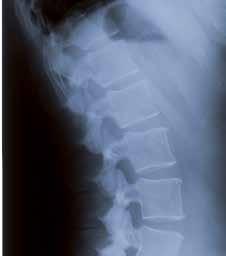

Radiografia di una colonna vertebrale con morfologia normale ( incidenza laterale)

Colonna con collasso vertebrale (incidenza laterale)

Raggi X

Una semplice radiografia non consente né di diagnosticare con sicurezza, né di escludere l’osteoporosi. Se, però, l’osteoporosi è già avanzata (oltre il 30 %), la

radiografia può indicarne la presenza. Se più vertebre risultano fratturate, vi è allora un’elevata probabilità di osteoporosi conclamata. L’osteoporosi non può essere diagnosticata o esclusa con certezza mediante una radiografia.